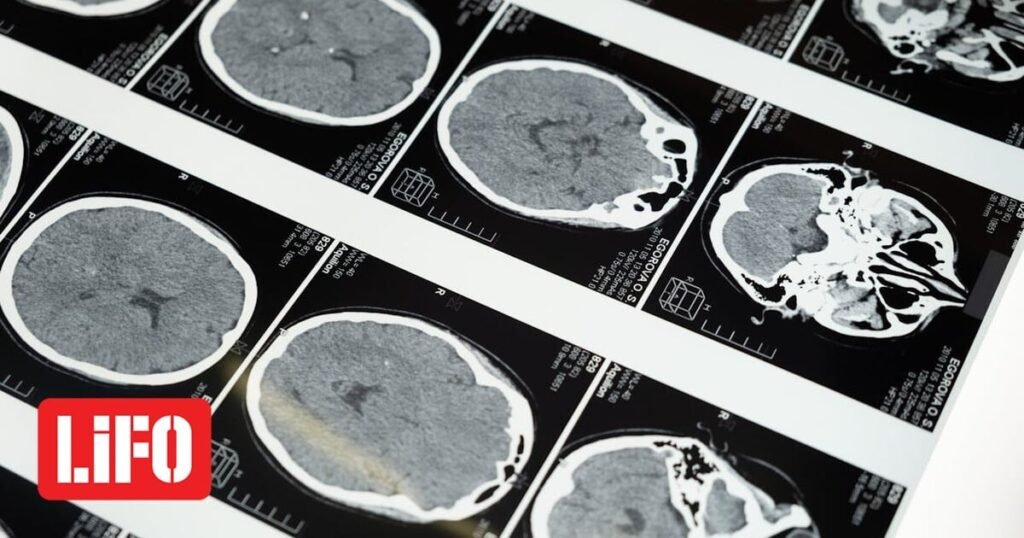

Το ανεύρυσμα εγκεφάλου είναι ένα αδύναμο ή λεπτό σημείο σε μια αρτηρία του εγκεφάλου, το οποίο διογκώνεται και γεμίζει με αίμα. Το ανεύρυσμα μπορεί να ασκήσει πίεση στα νεύρα ή στον εγκεφαλικό ιστό. Μπορεί επίσης να πάθει ρήξη, χύνοντας αίμα στον περιβάλλοντα ιστό (που ονομάζεται αιμορραγία).

Η ρήξη ενός ανευρύσματος μπορεί να προκαλέσει σοβαρά προβλήματα υγείας όπως αιμορραγικό εγκεφαλικό επεισόδιο, εγκεφαλική βλάβη, κώμα, ακόμη και θάνατο.

Ορισμένα ανευρύσματα εγκεφάλου, ιδιαίτερα αυτά που είναι πολύ μικρά, δεν αιμορραγούν ή προκαλούν άλλα προβλήματα. Αυτοί οι τύποι ανευρυσμάτων συνήθως ανιχνεύονται κατά τη διάρκεια απεικονιστικών εξετάσεων για άλλες ιατρικές καταστάσεις.

Τα ανευρύσματα μπορούν να εμφανιστούν οπουδήποτε στον εγκέφαλο, αλλά τα περισσότερα σχηματίζονται στις κύριες αρτηρίες κατά μήκος της βάσης του κρανίου. Όλα τα ανευρύσματα εγκεφάλου έχουν τη δυνατότητα να πάθουν ρήξη και να προκαλέσουν αιμορραγία στον εγκέφαλο ή στη γύρω περιοχή.

Τα ανευρύσματα εγκεφάλου ταξινομούνται ανάλογα με το μέγεθος σε μικρά, μεγάλα, και γιγάντια και κατά σχήμα σε σακοειδή (σαν μούρα), ατρακτοειδή και μυκωτικά. Τα σακοειδή ανευρύσματα είναι ο πιο κοινός τύπος και μπορεί να προκύψουν από διάφορους παράγοντες κινδύνου, όπως γενετικές καταστάσεις, υπέρταση, κάπνισμα και κατάχρηση ναρκωτικών.

Περίπου το 85% των ανευρυσμάτων εντοπίζονται στην πρόσθια κυκλοφορία, κυρίως σε διακλαδώσεις κατά μήκος του κύκλου του Willis.

Τα συμπτώματα ενός μη ραγέντα ανευρύσματος είναι συχνά ελάχιστα, αλλά μία ρήξη ανευρύσματος μπορεί να προκαλέσει σοβαρούς πονοκεφάλους, ναυτία, διαταραχή της όρασης και απώλεια συνείδησης, οδηγώντας σε υπαραχνοειδή αιμορραγία.

Οι θεραπευτικές επιλογές περιλαμβάνουν μικροχειρουργικό αποκλεισμό (clipping) και ενδαγγειακή περιτύλιξη (coiling), που στοχεύουν και τα δύο στην πρόληψη περαιτέρω αιμορραγίας.

Η διάγνωση συνήθως περιλαμβάνει απεικονιστικές τεχνικές όπως αξονική, μαγνητική ή ψηφιακή αγγειογραφία και οσφυονωτιαία παρακέντηση για την ανίχνευση της υπαραχνοειδούς αιμορραγίας.

Η πρόγνωση εξαρτάται από παράγοντες όπως το μέγεθος και η θέση του ανευρύσματος και η ηλικία και η υγεία του ασθενούς, με τα μεγαλύτερα ανευρύσματα να έχουν υψηλότερο κίνδυνο ρήξης και χειρότερη εξέλιξη.